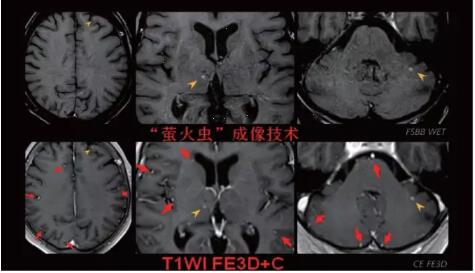

見所未見 微小腫瘤無處遁藏——

“螢火蟲”成像技術(shù) 顱內(nèi)腫瘤微小病灶檢出新發(fā)現(xiàn)

此技術(shù)主要用于神經(jīng)系統(tǒng)惡性腫瘤,以及其他腫瘤腦轉(zhuǎn)移瘤篩查。傳統(tǒng)情況下做腫瘤腦轉(zhuǎn)移篩查,很容易漏掉5mm以下小病灶,臨床發(fā)現(xiàn)后干預(yù)治療比較晚,要實現(xiàn)2mm高空間分辨率和超薄層全腦掃描在保證信噪比的情況下需要很長時間大概十多分鐘,而且薄層增強序列顱內(nèi)血管呈高亮信號,會干擾顱內(nèi)小病灶的觀察,血管和小病灶區(qū)分困難。佳能”螢火蟲”成像技術(shù)既可以實現(xiàn)高空間分辨率和超薄層(最薄可實現(xiàn)0.2mm)全腦掃描,掃描時間短,2-3分鐘即可實現(xiàn)全腦3D掃描,同時避免了血管高亮信號的干擾,對顱內(nèi)原發(fā)或繼發(fā)的微小腫瘤檢查有重大意義。“螢火蟲”成像技術(shù)具有磁敏感效應(yīng),對于亞急性血敏感敏感,可以區(qū)分出血和強化的腫瘤。